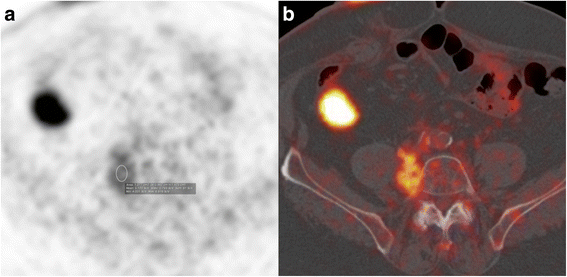

Case presentation: A 75 year-old patient was treated for a high grade transitional cell carcinoma of the bladder by surgery, chemotherapy and radiotherapy. Histology showed foci of bone metaplasia, both at the periphery of the tumor, and in a lymph node metastasis. 1 year later, a heterotopic bone formation was discovered in the right retroperitoneal space, near the lumbar spine, increasing rapidly in size during follow-up. Several imaging exams were performed (2 CT, 1 MRI, 1 Pet-CT), but in the absence of typical features of sarcoma, diagnosis remained unclear. Histology of a CT-guided percutaneous biopsy showed urothelial carcinoma and mature lamellar bone. Integration of these findings with the radiological description of extraosseous localization was consistent with a diagnosis of osseous metaplasia of an urothelial carcinoma metastasis. The absence of bone atypia in both the primary and metastases argues against sarcomatoid urothelial carcinoma with osteosarcomatous differentiation.

Conclusion: Osseous metaplasia of an urothelial carcinoma metastasis is unusual, and difficult to distinguish from radiotherapy induced sarcoma, or from sarcomatoid carcinoma. Rapid progression, sheathing of adjacent structures such as vessels (like inferior vena cava in our case) and nerves and bony feature of lymph node metastases necessitate histological confirmation and rapid treatment. Our case illustrates this disease and evaluates the imaging features. In addition we discuss the differential diagnosis of osseous retroperitoneal masses.